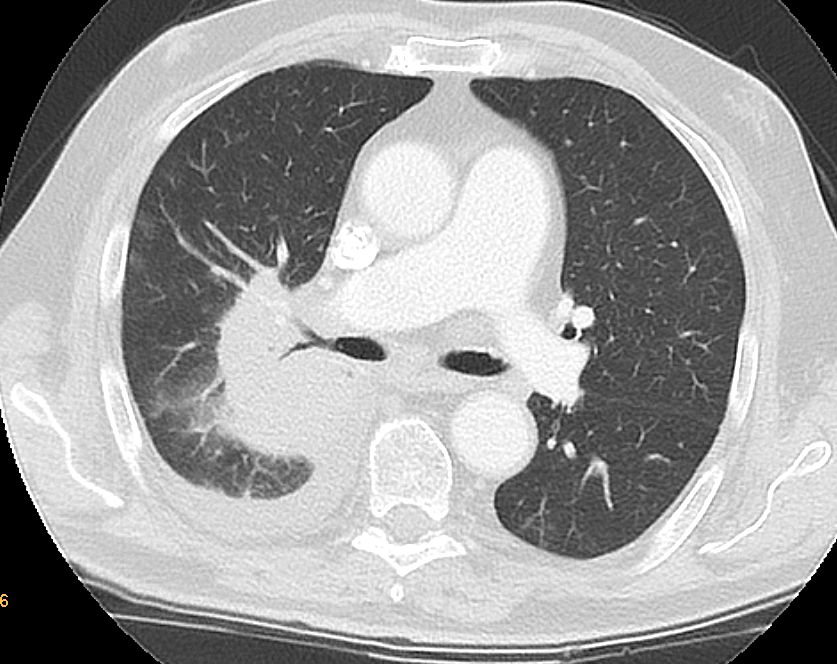

Lungen - Metastasen

70-jähriger Mann, der vor 8 Jahren ein Prostata-Karzinom pT3b, pN1(2/17) Mo Gleason 7 PSA 6,75 entwickelte. Radikale Prostatovesikulektomie, postoperative RT des pelvinen LA und der Prostataloge. LHRH-Analoga. Vor 7 Monaten wurde eine 10cm große Metastasierung in den rechten Lungenhilus festgestellt. Nach 6 Monate Dozetaxel nur geringe Größenabnahme.